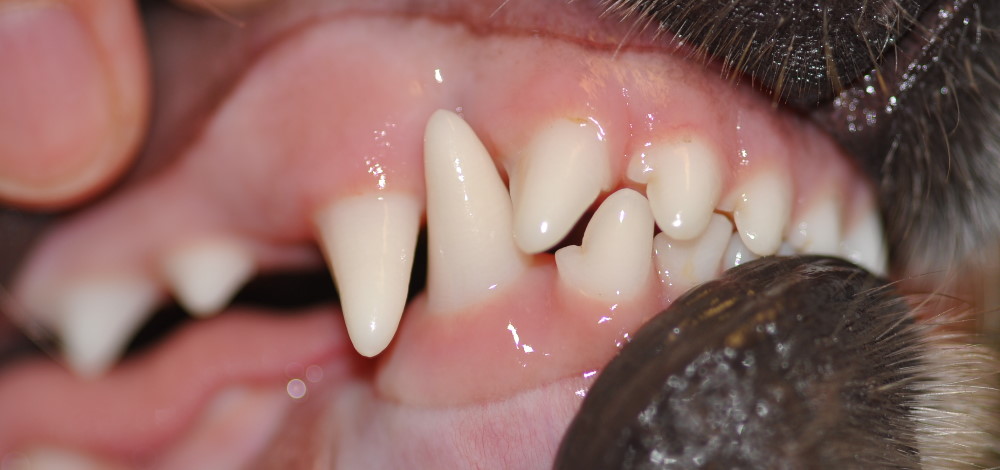

Zahnfrakturen, Zahnfüllungen, Korrektur von Fehlstellungen (Brekkets)

Insbesondere bei Rasse- und Zuchtieren aber auch bei Nutz- und Jagdhunden wird auf die Vollständigkeit und die perfekte Zahnstellung des Gebisses großen Wert gelegt. Deshalb besteht bei uns die Möglichkeit zur Korrektur von Zahnfehlstellungen und zahnerhaltenden Füllungen.